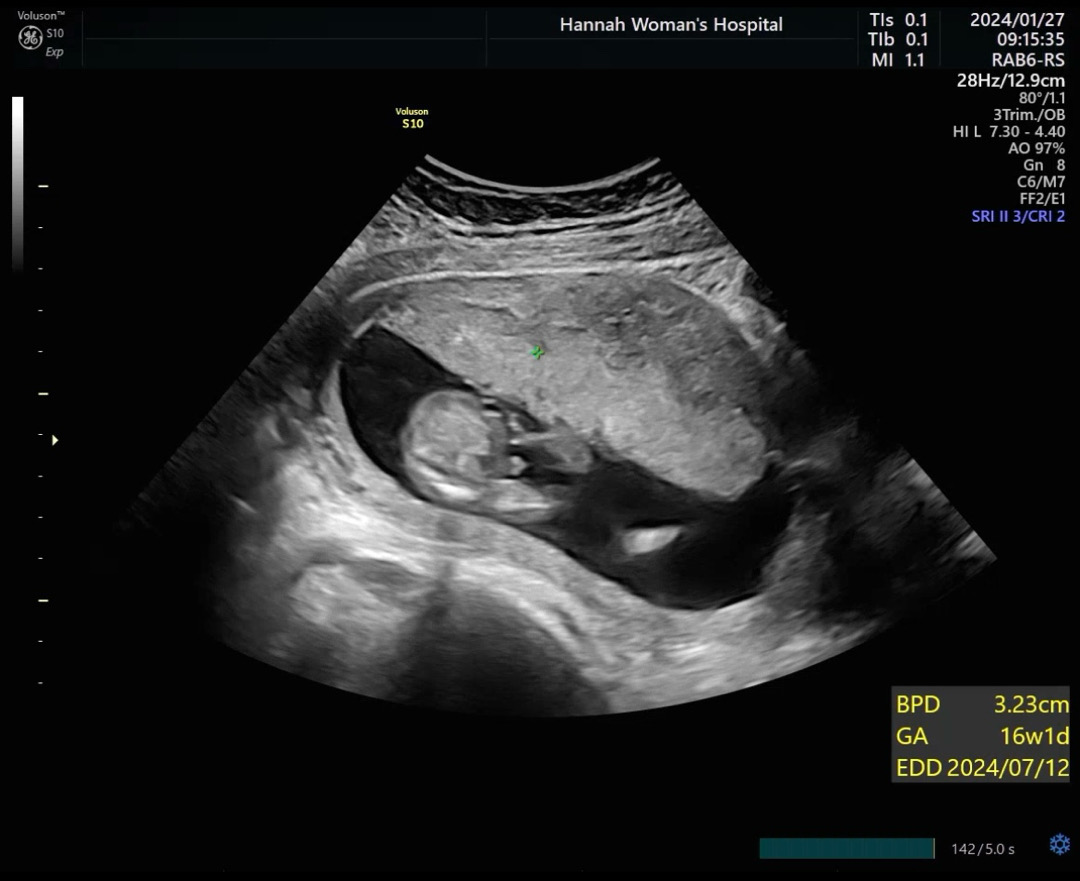

16주차 아들맘 확정받고 왔네요~🥰 고튜 존재감 확실해서 너무 귀엽고 벌써부터 사랑스러워요 앞으로 건강하게 잘커서 얼른 만났으면 좋겠네요🩵